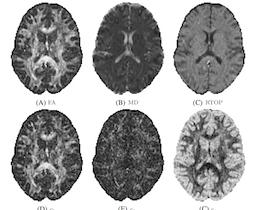

Modern diffusion magnetic resonance imaging (dMRI) acquires intricate volume datasets and biological meaning can only be found in the relationship between its different measurements. Suitable strategies for visualizing these complicated data have been key to interpretation by physicians and neuroscientists, for drawing conclusions on brain connectivity and for quality control. This article provides an overview of visualization solutions that have been proposed to date, ranging from basic grayscale and color encodings to glyph representations and renderings of fiber tractography. A particular focus is on ongoing and possible future developments in dMRI visualization, including comparative, uncertainty, interactive and dense visualizations.